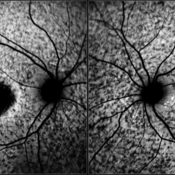

Optic nerve head drusen

Dec 26 2022 by Vaidehi Sathaye

FAF photograph of LE of a 32 year old female with Optic nerve head drusen

Photographer: Dr. Vaidehi Sathaye

Imaging device: Mirante

Condition/keywords: drusen of optic disc

Fundus Photograph of LE of a 32 year old female with Optic nerve head drusen